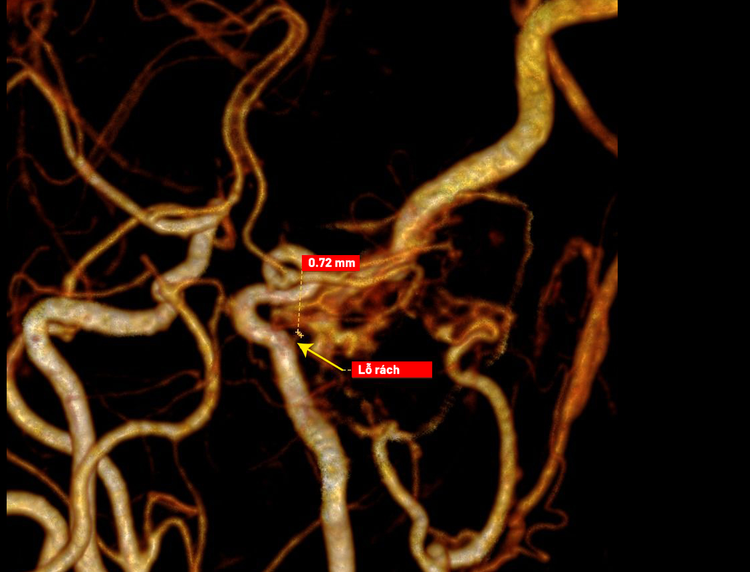

Nhờ chụp bằng “siêu máy” CT Somatom Force VB30 với độ phân giải rất cao, bác sĩ phát hiện được điểm rò mạch chỉ khoảng 0,7 mm - kích thước cực nhỏ và nằm ở vị trí khó tiếp cận, gần như không thể nhận diện nếu sử dụng CT thông thường.

Hơn 100.000 lát cắt trong một lần chụp, khảo sát toàn bộ hệ mạch chi tiết. Lát cắt mỏng chỉ 0,4 mm, giúp phát hiện chính xác các tổn thương mạch máu rất nhỏ.

Dựng hình 3D - 4D toàn bộ mạch máu, quan sát rõ cấu trúc và dòng chảy. Xác định chính xác vị trí điểm rò và hướng rò trong xoang hang. Hỗ trợ bác sĩ lập kế hoạch can thiệp phù hợp, an toàn và chính xác.

Hình ảnh rò động mạch cảnh xoang hang trên phim chụp - Ảnh BVCC